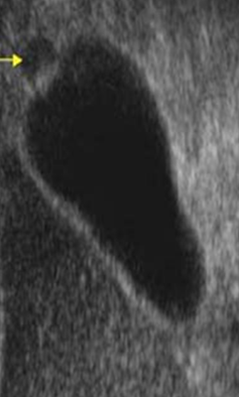

This asymptomatic 2nd year med student was practicing ultrasound on himself when he found the attached image. Concerned he asks you what you think is going on.

You, being a jerk answer… “ooh that looks like gallstones for sure.” Before telling him that you’re kidding and that it actually is?

A phyrigian cap denotes folding of the fundus back upon the gallbladder body.

•Although clinically unimportant, it may be mistaken on ultrasound examination for septation or possibly stone